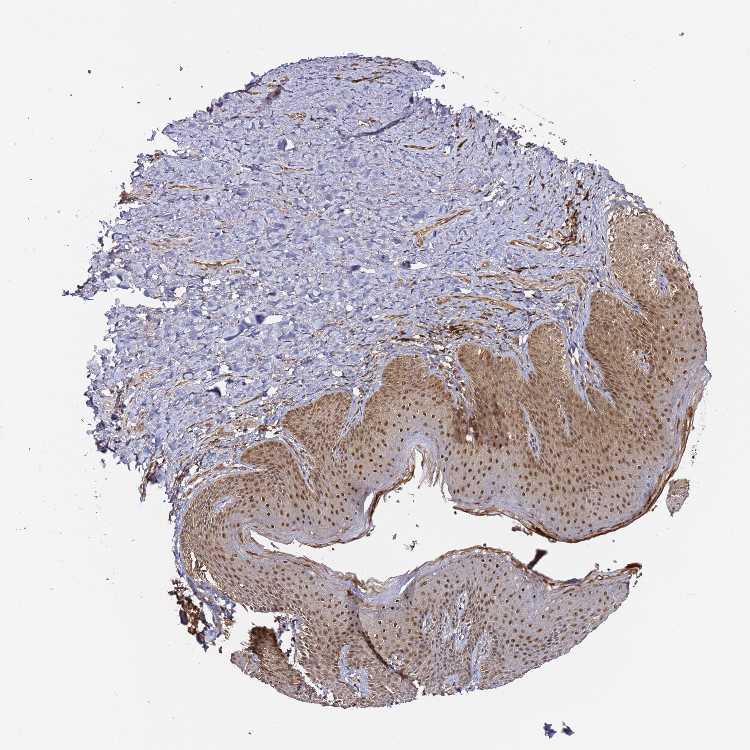

SKIN 2 - Antibody stainingi

Antibody staining in the annotated cell types in the current human tissue is reported as not detected, low, medium, or high, based on conventional immunohistochemistry profiling in selected tissues. This score is based on the combination of the staining intensity and fraction of stained cells.

Each image is clickable and will lead to virtual microscopy that enables deeper exploration of all samples and also displays staining intensity scores, fraction scores and subcellular localization as well as patient and tissue information for each sample.

Antibody HPA045780

Epidermal cells Medium